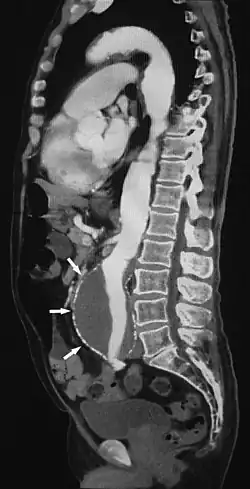

L'angioscanner, appelée aussi angioscopie, est un examen d'imagerie médical qui permet la visualisation des vaisseaux sanguins qui ne sont habituellement pas visibles par radiographie standard. Il fonctionne avec l'injection d'un produit de contraste iodé visible au scanner par l'action des rayons X le rendant opaque[1].

Cela permet de détecter tout problème vasculaire, comme une sténose, en plus de cartographier le réseau vasculaire, par exemple avant une intervention chirurgicale[2].